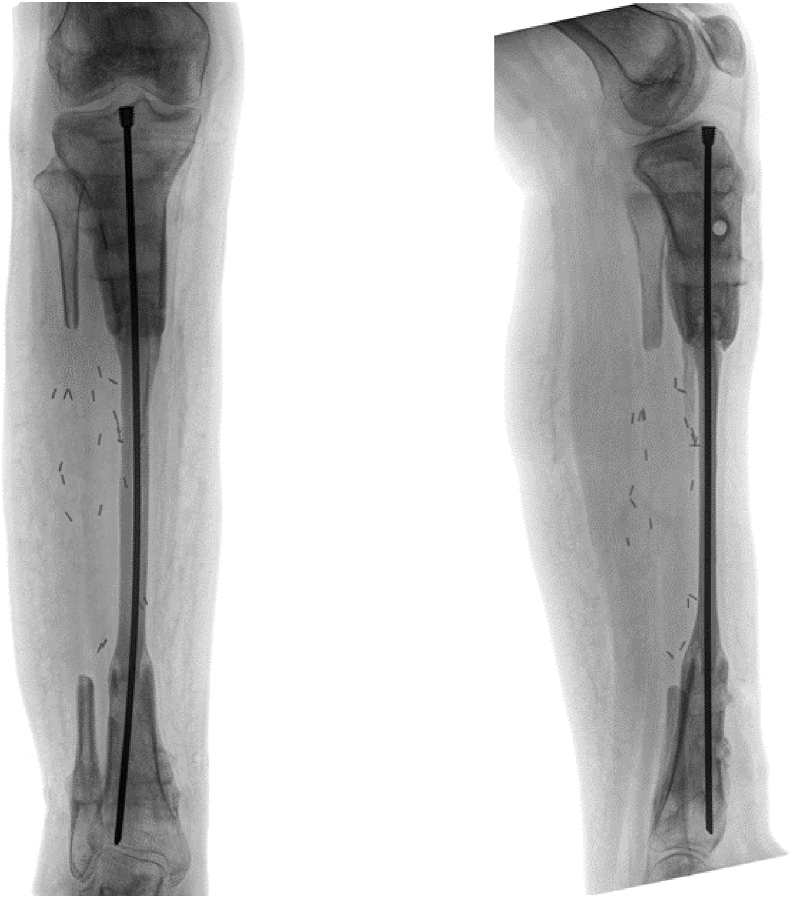

A 12+9-year-old female-assigned at birth diagnosed with osteofibrous dysplasia of her right tibia underwent 15cm bone resection, ipsilateral pedicled fibular graft, and frame application without a thorough multidisciplinary preoperative evaluation. During her course of treatment, the patient's mood and ability to participate in her own care (e.g. showering, feeding herself on a regular and consistent basis, completing home exercises) declined precipitously, and she began to endorse symptoms of suicidal ideation and non-suicidal self-injury behavior. Eventually the patient had to be admitted to the team's pediatric orthopaedic institution and was later transferred to an intensive outpatient mental health program for safety and mood stabilization. Due to multiple absences, the patient was prematurely dismissed from the mental health program and subsequently refused to participate with any sort of mental health intervention. Simultaneously, she struggled to cope with the demands of her external fixation treatment.Broadly, this case highlights the critical importance of thorough psychological assessment prior to consideration of limb lengthening and/or reconstruction. Psychological assessment should first establish the patient's baseline mental health, identify any extant mental health symptoms, and connect the patient with appropriate intervention as needed. Second, psychological assessment should establish the family's baseline functioning, including caregiver availability and support as well as emotional and logistical resources available to support treatment. Third, psychological assessment should continue throughout the course of treatment, in order to identify real time possible changes in a patient's mental health and intervention needs.

一名12+9岁女性,出生时被诊断为右胫骨骨纤维性发育不良,在没有进行全面的多学科术前评估的情况下,接受了15cm骨切除、同侧带蒂腓骨移植和框架应用。在治疗过程中,患者的情绪和参与自我护理的能力(如洗澡、定期和持续地自己进食、完成家庭运动)急剧下降,并开始出现自杀意念和非自杀自残行为的症状。最终,患者不得不住进该团队的儿科骨科机构,随后被转移到一个强化的门诊心理健康项目,以确保安全和情绪稳定。由于多次缺席,患者被过早地从心理健康项目中解雇,随后拒绝参加任何形式的心理健康干预。同时,她也在努力应对外固定治疗的要求。总的来说,这个病例强调了在考虑肢体延长和/或重建之前进行彻底的心理评估的重要性。心理评估应首先确定患者的心理健康基线,确定任何现存的心理健康症状,并根据需要将患者与适当的干预联系起来。第二,心理评估应该建立家庭的基本功能,包括照顾者的可用性和支持,以及支持治疗的情感和后勤资源。第三,心理评估应在整个治疗过程中持续进行,以便实时识别患者心理健康和干预需求的可能变化。关键概念:(2)术前心理评估应建立患者的基线心理健康状况,并确定任何先前存在的心理健康问题。(3)术前心理评估应建立患者的家庭基线功能,重点关注认知、(4)心理评估应在整个治疗过程中持续进行,以便及时识别治疗过程中出现的任何情绪问题。